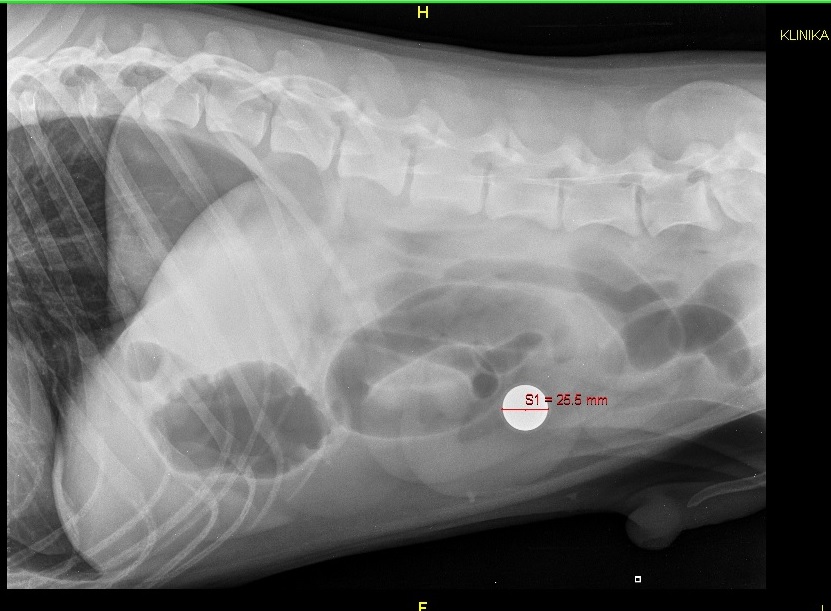

3. Witam, dzisiaj mój kochany pies przeszedł zabieg z powodu niedrożności jelit. Po zrobieniu zdjęcia rtg myśleliśmy z weterynarzem, że połknął jakąś monetę. Weterynarz długo się męczył, żeby znaleźć w brzuszku ciało obce, aż w końcu udało mu się wyciągnąć ciężką kulkę. Wydawało mi się, że jest to kulka od starych myszek ponieważ one też były ciężkie i osłonięte gumą jednak gdy wróciłam do domu wygrzebałam z szafy starą myszkę i szybko okazało się, że kulka, którą połknął jest większa. Ktoś z Was ma pomysł co to takiego jest? Może to jednak kulka od myszki, jakiś inny typ? Jeśli tak to orientujecie się jaki metal jest w środku? Dołączam zdjęcia, Pozdrawiam K ;)

2. Ta obok do porównania to właśnie ta kulka, którą wyjęłam z myszki. Właśnie zastanawiałam się, że może ta, którą znalazł i połknął jest z jakiejś myszki innego typu, ale jednak wydaje mi się, że te kulki są uniwersalne jednakowej wielkości niezależnie od wielkości myszki w każdym razie chciałam się zapytać o to Was bo mi już nic nie przychodzi do głowy. Piesek nadal otumaniony. Zabieg miał o 15:30 do około 17. Od tamtej pory spał i teraz próbował wstać choć nadal nie ma siły.Leżał cały czas na boku teraz lekko zgarbiony położył się na brzuch i troche się martwie żeby przez to nie naruszył sobie zszytego jelita. Może macie dla mnie jakieś rady? Wybaczcie, że zawracam głowę, ale piesek to moje oczko w głowie i jestem przerażona chyba bardziej od niego...;)